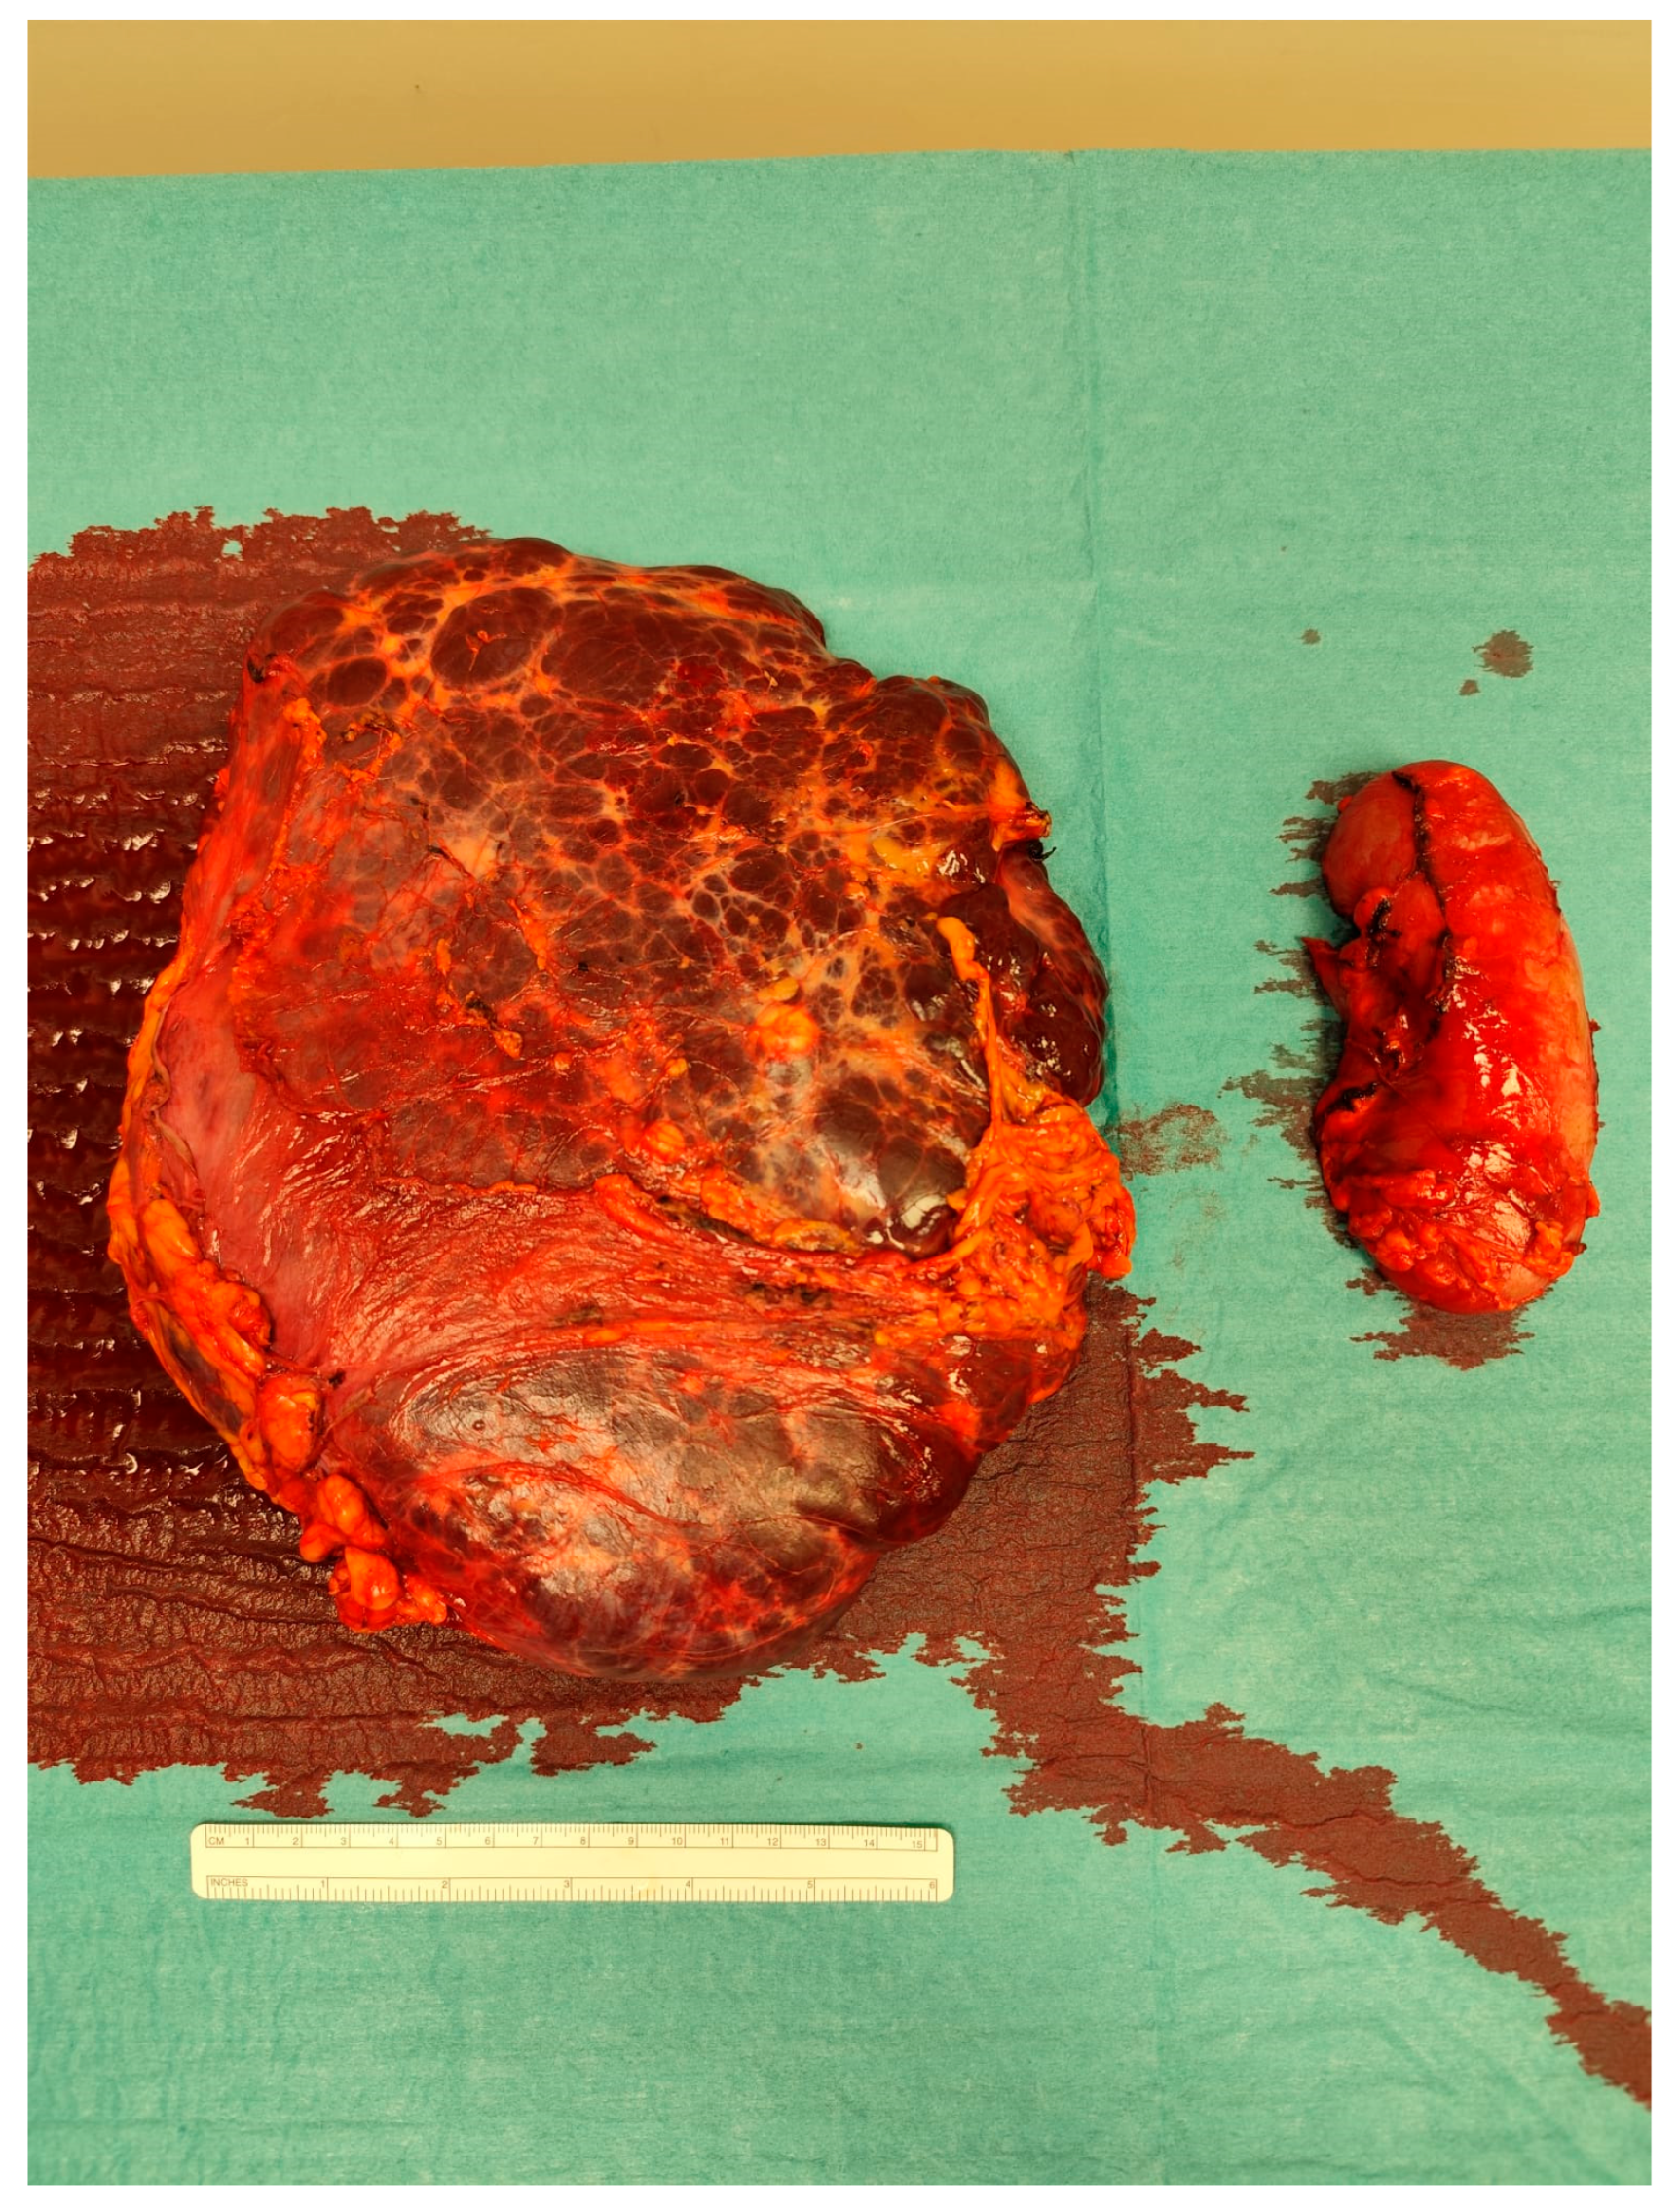

The case was discussed during the dedicated multi-disciplinary meeting, and due to the lesion’s considerable size and complex structure, as well as the inconclusive results of the biopsy, surgical resection was advised. The procedure included “en bloc” removal of the left kidney and adrenal gland, both of which were tightly adherent to the mass (Figure 4 and Figure 5).

Postoperative pathological examination revealed a brownish, multiloculated cystic lesion measuring 18 × 17 × 30 cm, with areas of hemorrhage and multiple whitish calcified components. Subsequent analysis identified these calcifications as phleboliths, formed secondary to intralesional thrombotic events.

Figure 4. Intraoperative picture showing the mass.

Figure 5. The resected specimen.